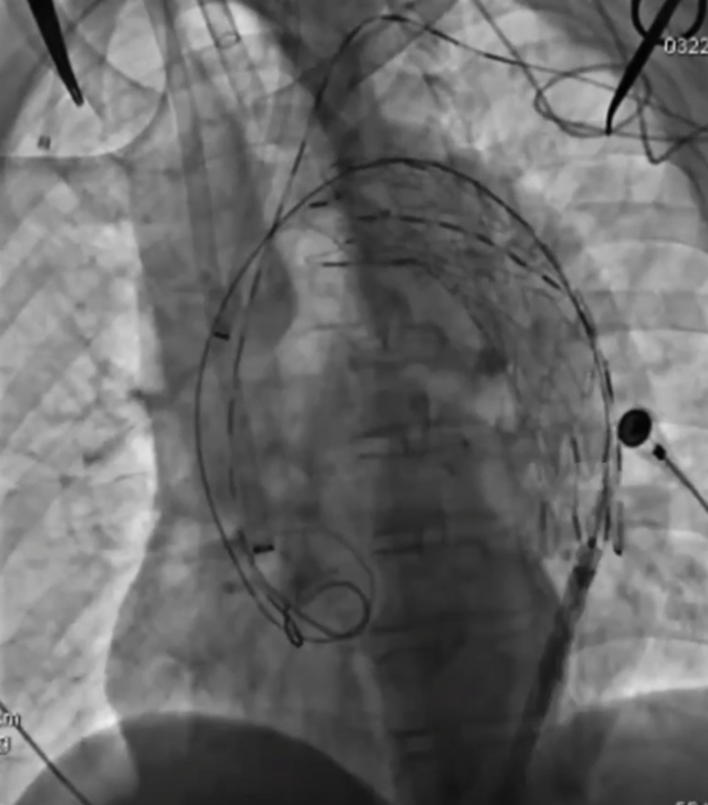

手术过程(三):调整左颈总动脉导管鞘位置,使其抵于戈尔支架表面,跟进球囊导管及激光光纤,行激光原位开窗。开窗成功后,自开窗口植入V18导丝,跟进Sterling球囊导管,行球囊扩张,扩张完成后交换为硬导丝。植入Fluency覆膜支架,完成左颈总动脉重建。

波科支架怎么样陆信武:激光原位开窗重建弓上分支治疗A型主动脉夹层_https://www.jmylbn.com_新闻资讯_第6张

手术过程(四):回撤头臂干导管鞘,使其抵于戈尔支架表面,同样方法行激光原位开窗。开窗成功后,先前推进球囊,进入覆膜支架,交换硬导丝后行球囊扩张。植入覆膜支架,完成头臂干动脉重建。

波科支架怎么样陆信武:激光原位开窗重建弓上分支治疗A型主动脉夹层_https://www.jmylbn.com_新闻资讯_第7张